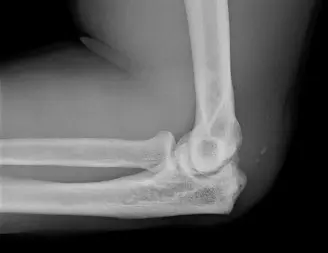

صورة توضيحية لـ تمزق وتر العضلة ثلاثية الرؤوس: دليل شامل للمرضى مع الأستاذ الدكتور محمد هطيف

صورة سريرية توضح عيبًا محسوسًا فوق المرفق بعد تمزق وتر ثلاثية الرؤوس